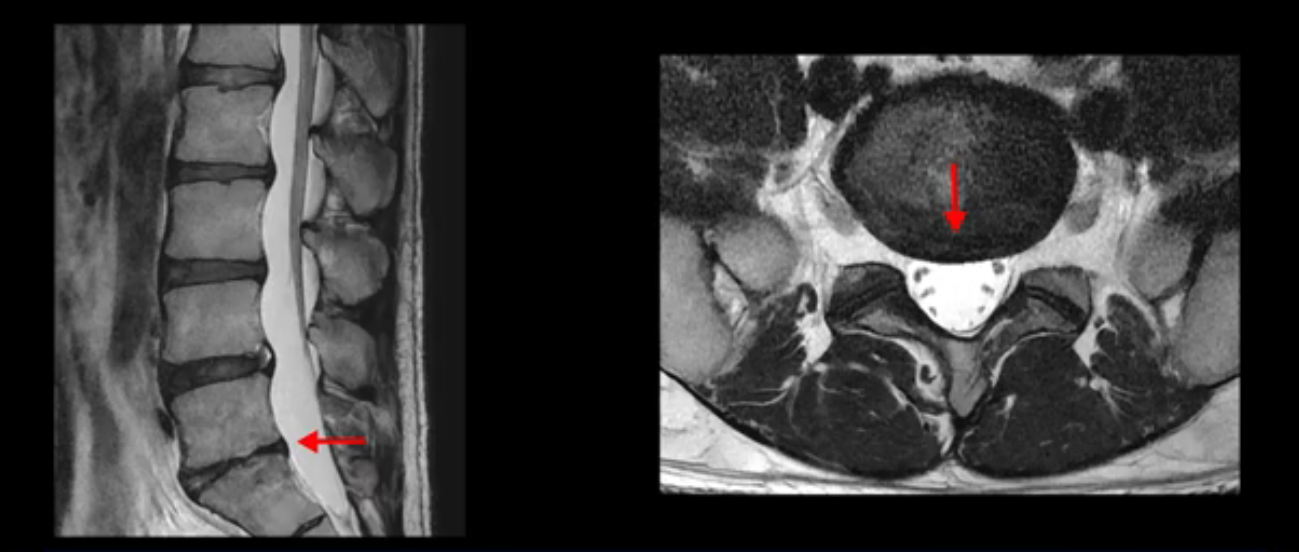

우선 이분 MRI를 보면 허리 모든 마디의 디스크가 퇴행되어 있고

여러 마디의 디스크가 조금씩 밀려나와 보이고, 디스크 섬유륜도 찢어져 보이는 마디도 보입니다.

그런데 이분의 증상과 MRI가 전혀 일치하지 않는데, 왜 그런지 지금부터 자세히 설명드립니다. 이분 증상은 앉으면 엉치와 허리가 심하게 아파 10분 이상 앉는 게 어렵고 양쪽 발가락이 앉아있을 때나 누워있을 때 다 저립니다. 걸을 때도 아파서 10분 걷기도 어렵습니다. MRI를 마디마디 살펴보면 1번 2번은 오른쪽으로 살짝 밀려나온 디스크가 있지만 전혀 심하지 않고, 뒤에 또 설명하겠지만 최근에 밀려나온 급성 디스크가 아니고 오래된 디스크로 판단됩니다.

2번 3번도 비교적 디스크 상태는 좋고 신경 구멍 넓이도 아주 넓습니다.

3번 4번도 마찬가지로 디스크상태 좋아 보이고 신경 눌림 전혀 없어 보입니다.

4번 5번은 가운데로 섬유륜이 찢어져서 디스크가 살짝 밀려나와 있지만 역시나 최근에 찢어지고 밀려나온 걸로 판단되지 않고 오래 전에 찢어진 흔적으로 보입니다.

왜 최근에 찢어진 급성이 아니고 오래된 거라고 하는지 이 부분도 뒤에 한꺼번에 설명 드리겠습니다.

5번 1번 역시 가운데로 디스크 조금 밀려 나와있지만 신경 공간 넓이는 아주 넓어서 신경 눌림 있을 거라고 예상이 안됩니다.

추간공도 보시다시피 왼쪽, 오른쪽 전부 다 매우 넓어서 신경이 눌릴만한 부분이 전혀 보이지 않습니다.

앞서 1번 2번, 4번 5번, 5번 1번의 디스크가 찢어지고 조금 밀려 나온 게 최근에 찢어진 게 아니고 오래된 걸로 보인다고 말씀 드렸죠. 왜 그럴까요? 만약 급성으로 찢어진 것이라면 아주 심한 디스크성 통증이 있겠죠. 기침이나 재채기를 하면 심하게 아프고 허리를 조금만 구부리거나 비틀면 아주 날카로운 통증들이 생길 겁니다. 그런데 이분은 이런 증상이 전혀 아닙니다. 또 디스크의 밀려나온 정도도 전혀 심하지 않기 때문에 이분이 가지고 계신 양쪽 다리 저림, 특히 이분은 누워있을 때도 양쪽 발이 발가락까지 쑤신다고 하는데 이정도 디스크 때문에 그런 증상은 생길 수가 없는 겁니다. 이처럼 이분의 가벼운 디스크 탈출은 이미 오래 전에 진행되었고 섬유륜 자체는 이미 아문 상태인데도 디스크내장증을 진단받은 환자들 중에는 본인이 섬유륜 파열 환자라고 끝까지 믿는 분들이 많습니다. 다시 말하지만 디스크내장증이라는 진단을 받은 환자들을 보면 거의 전부 다 섬유륜 파열 증상이 아닙니다. 증상이 완전히 다릅니다. 진단이 애초에 잘못되면 어떤 치료를 받아도 좋아질 수 없습니다.

이분은 어떤 한 병원에서 디스크 내장증 얘기를 들으셨는데요. 여기 보시는 것처럼 4번 5번의 하얀 HIZ(High Intensity Zone)을 보고 디스크 내장증의 근거로 얘기하는 병원들이 있는데,

이 HIZ는 섬유륜이 찢어졌다가 이미 아문 뒤에도 얼마든지 보일 수 있는 흔적일 가능성이 있어서 재채기를 하면 아픈지, 허리를 구부릴 때 날카로운 통증이 생기는가 등의 증상으로 구별해야 하는데 MRI만 보고 HIZ가 보이면 그게 마치 통증의 원인인 것처럼 얘기하는 의사들이 있습니다. 이분 MRI를 자세히 보고 증상을 정말 자세히 들어본 의사가 있었더라면 다른 환자분들처럼 증상과 MRI가 일치하지 않는다는 얘기를 들을 수 있었을 텐데 이분은 그런 얘기는 듣지 못했습니다.